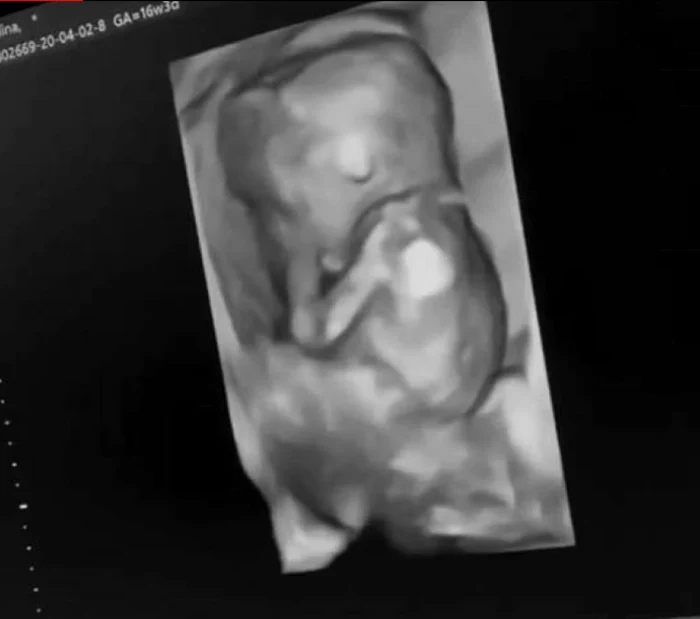

În fotografiile alb-negru postate apare îmbrăcată în haine sport, albe, iar burtica este evidentă. Mai mult decât atât, ea a distribuit imagini cu ecografia.